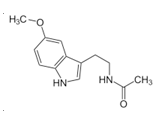

• Triptofan, 5-htp, Szerotonin

• Antidepresszánsok és az 5-HTP